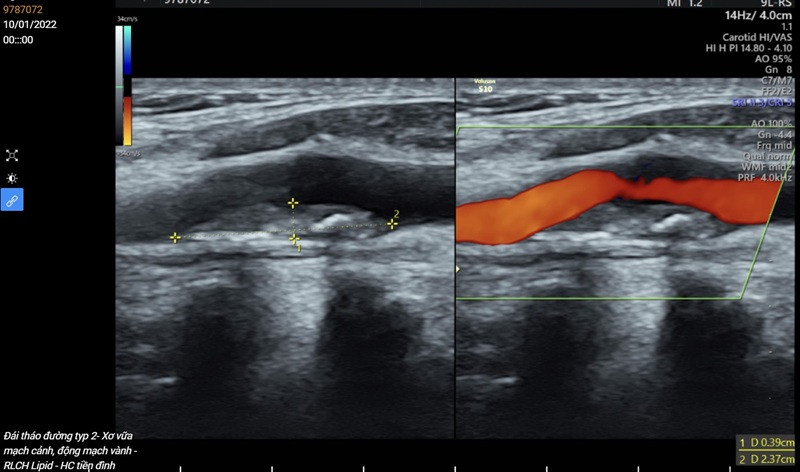

siêu âm động mạch cảnh (hay siêu âm Doppler mạch cảnh) là phương pháp chẩn đoán hình ảnh an toàn, không xâm lấn. Theo đó, máy siêu âm sẽ thu nhận tín hiệu từ đầu dò và tiến hành tái hiện hình ảnh mô tả mạch cảnh hiển thị trên màn hình theo dõi. Trong quá trình siêu âm, bác sĩ thường ghi lại quy trình quét hoặc chụp nhanh hình ảnh.

Siêu âm động mạch cảnh giúp phát hiện dấu hiệu bất thường tại một hoặc hai bên động mạch cảnh

Thông qua siêu âm Doppler mạch cảnh, bác sĩ có thể phát hiện các mảng bám (thường do chất béo, cholesterol, canxi hoặc một số hợp chất khác tích tụ lại) gây hẹp một hoặc hai bên động mạch cảnh, ảnh hưởng đến lưu lượng máu vận chuyển lên não. Một tên gọi khác của tình trạng này trong y khoa là bệnh động mạch cảnh.